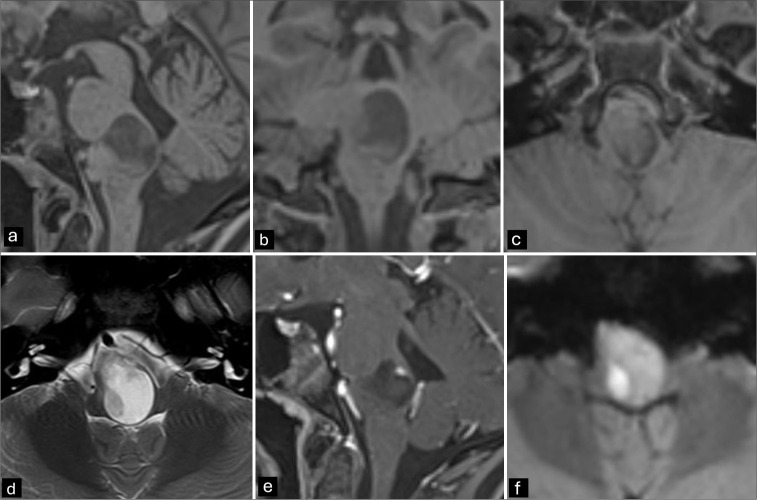

Background: Epidermoid cysts are slow-growing, rare congenital lesions. They are most seen in the cerebellopontine angle, fourth ventricle, or parasellar regions. Patients typically become symptomatic between 20- and 40 years of age. We present a rare case of a symptomatic intrinsic brainstem epidermoid cyst in a 12-year-old girl with atypical radiological features.

Case description: A 12-year-old girl presented with progressive gait disturbances, disequilibrium, diplopia due to right-sided abducens paresis, left-sided facial paresis (HB grade II), headaches, nausea, and vomiting over the past 6 months. Magnetic resonance imaging (MRI) revealed an intrinsic lesion of the brainstem not present on MRI 4 years prior. A microsurgical gross total resection, including resection of cyst wall, was performed. The pathology report diagnosed the lesion as an epidermoid cyst. The patient improved significantly after resection.